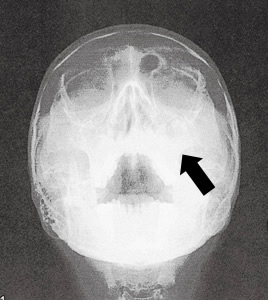

| ■慢性副鼻腔炎の場合 |

![]() |

| 両側の上顎洞は真白く写っている |